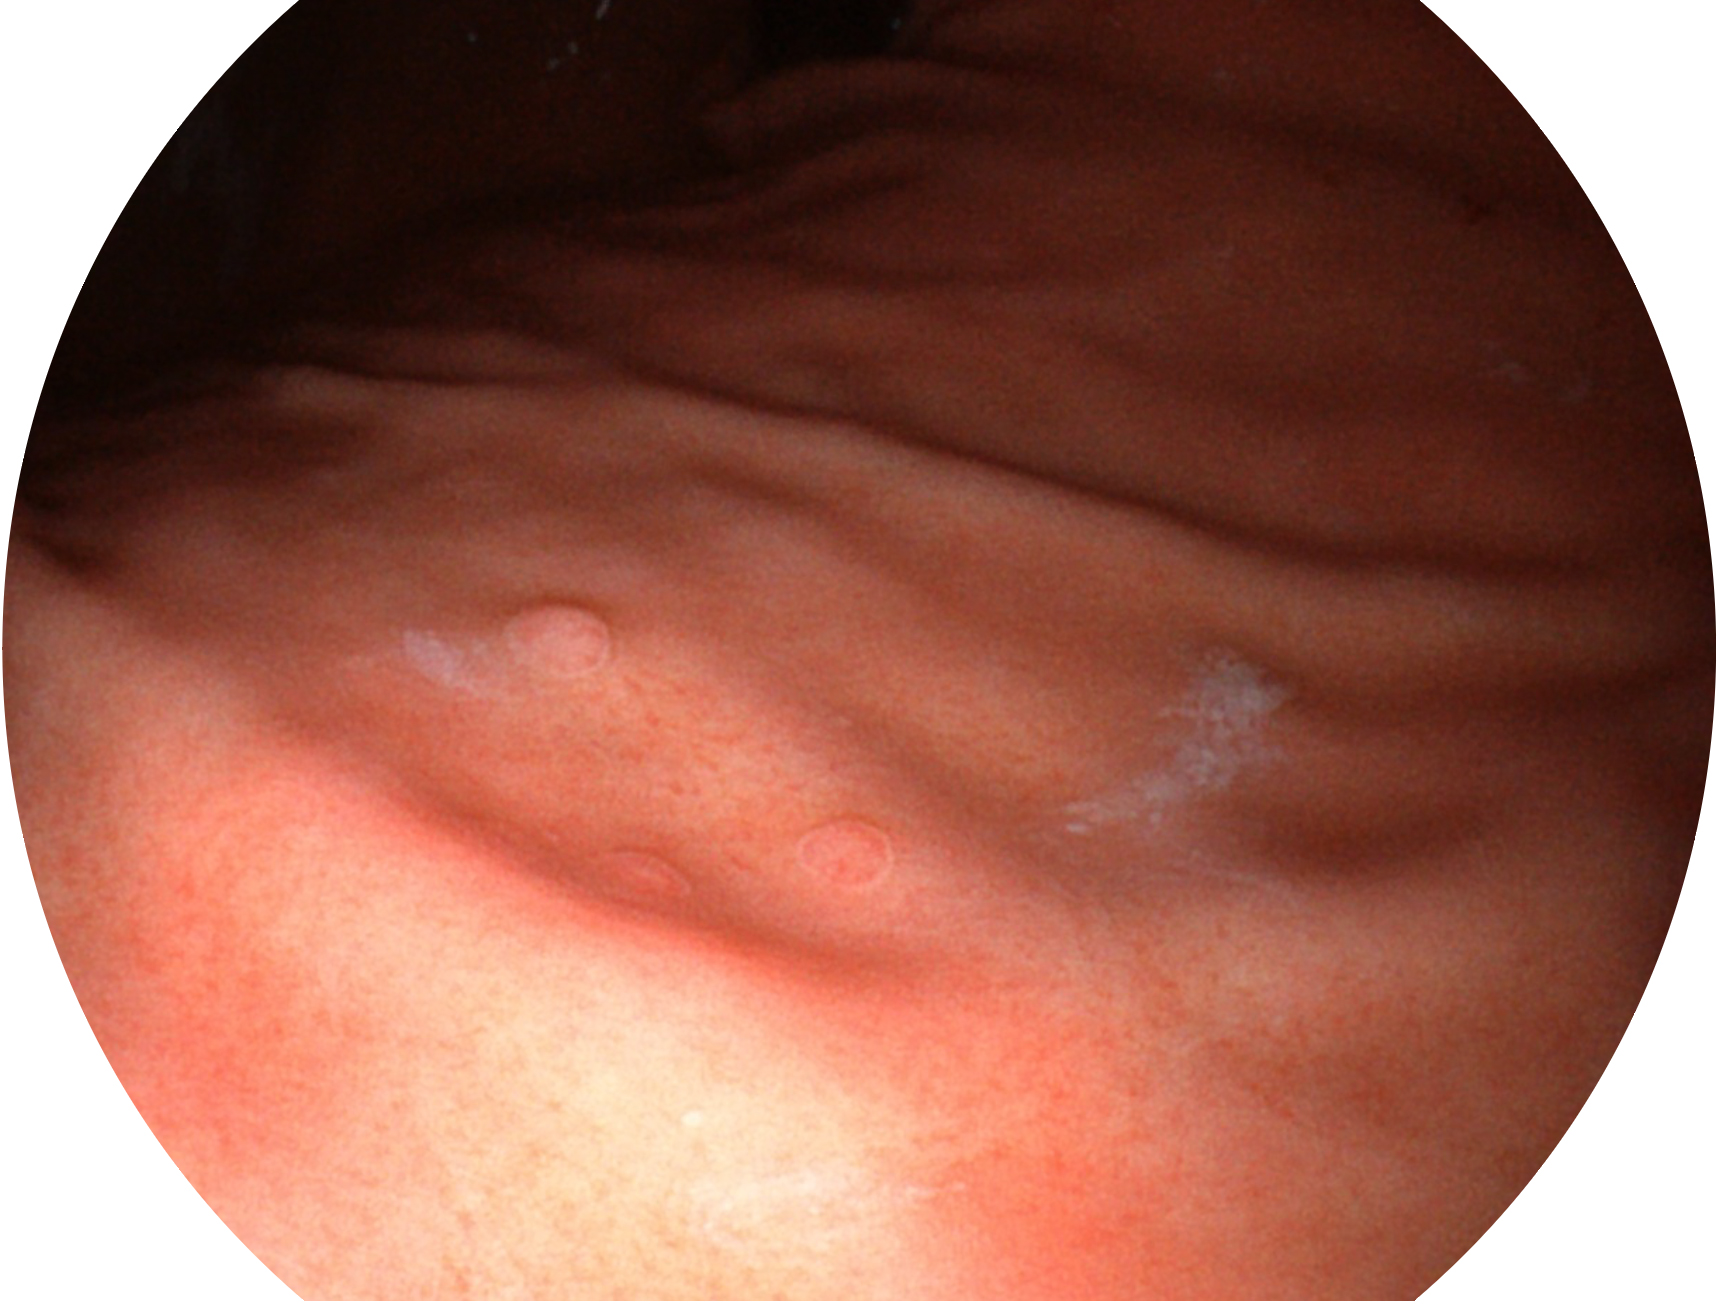

环球UG官网新开发的内镜染色技术,主要是基于多波长LED 光源的开发,VLS-55Q 四波长LED 光源是由四个不同颜色的LED光按照相应照明模式所规定的特定发光比例进行合束后形成,合束后形成的照明光的光谱由红光、绿光、蓝光及蓝紫光这四个不同的波段范围构成。具有更高光谱自由度,通过光谱比例的控制,实现了聚谱成像技术,英文全称为“Spectral Focused Imaging, SFI”,缩写为“SFI”和光电复合染色成像技术,英文全称为“Versatile Intelligent Staining Technology, VIST”,缩写为“VIST”。